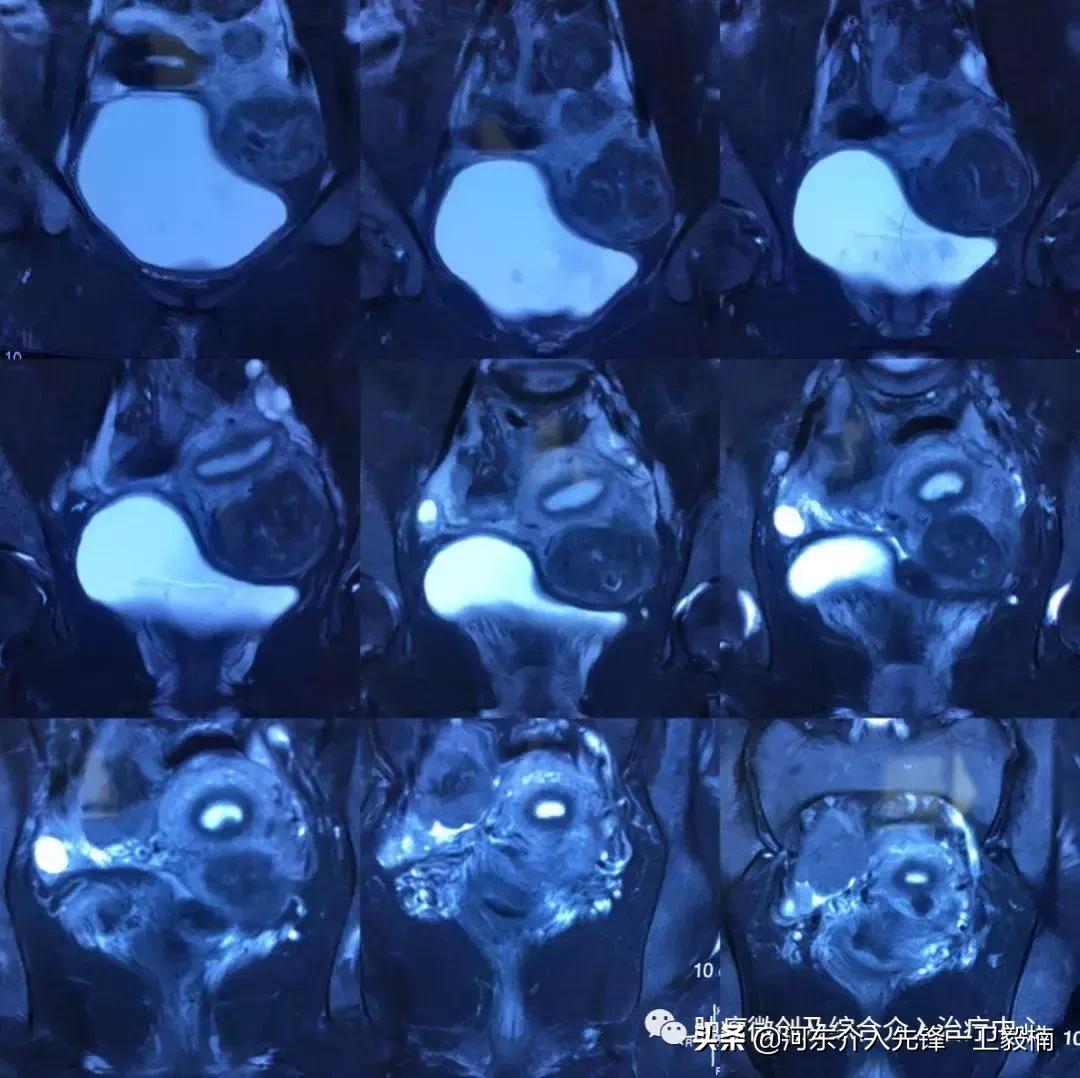

术前行MRI扫描: